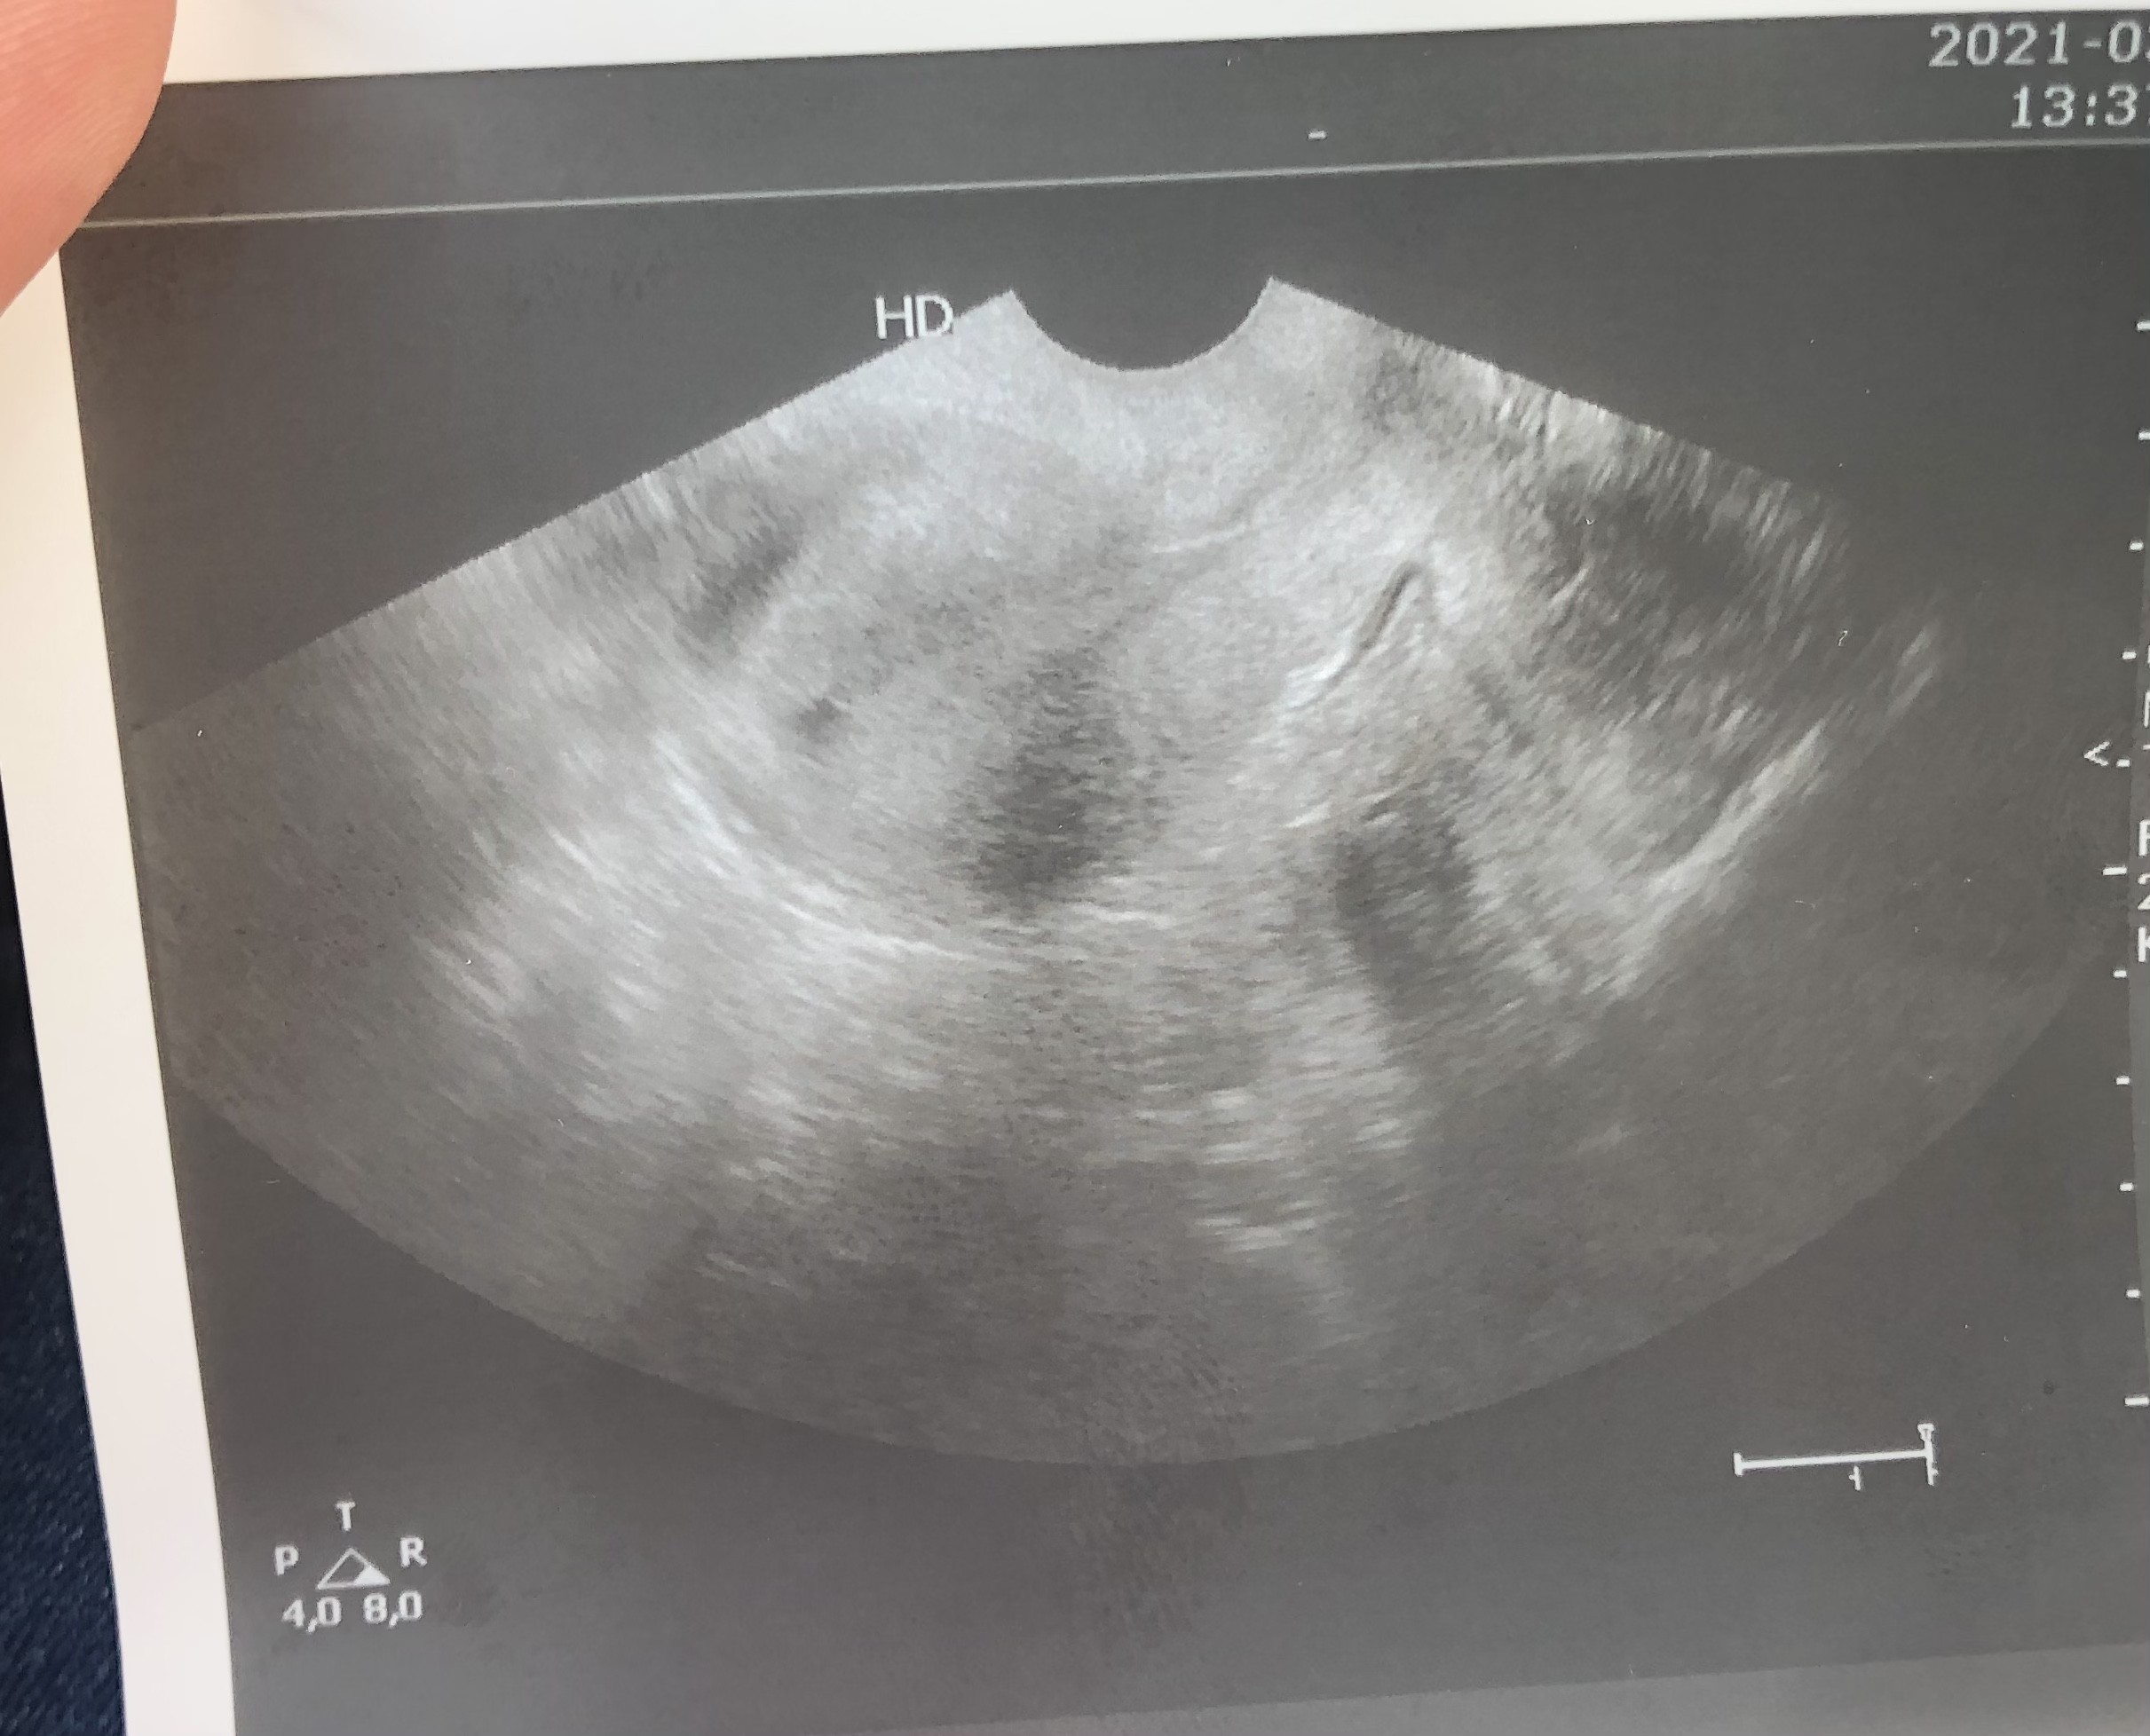

Dziewczyny czy Wy tu widzicie dwa pecherzyki? Doktor coś wspomniała, ze może są dwa, ale pewna jest tylko tego okrągłego. Ten obok chyba nie jest pęcherzykiem? Jak to u Was wyglądało w tym tygodniu? Beta rośnie o 300% co 48 h, wiec przyrost spory, ale w normie.

Nie znam się może ale bardzo dziwne to zdjęcie. Mega niewyraźne

Bardzo dziwne to zdjęcie powiem szczerze. A co mówił lekarz? Ja też prowadzę ciąże w medicover i zdjęcia są dużo wyraźniejsze, nie mówię że jakieś super ale jednak. Może tak trafiłaś akurat, u mnie faktycznie w jednym gabinecie jest gorszy sprzęt niż w drugim 🤗

Ja widzę aż 8 pęcherzyków 🤦🤷 ja miałam zdjęcie w 4 tc na też nienajlepszym sprzęcie, ale tam wyraźnie było widać jeden pęcherzyk w macicy.